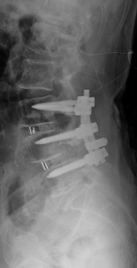

第4腰椎の前方へのすべりのため神経の圧迫を認めています。腰椎後方からずれを金属で整復固定し神経症状が改善しています。

階段状に腰椎が変性すべりをおこしている症例

【術前】

第2, 第3, 第4腰椎に前方への変性すべりを認めます。痛みのため背中を反って立てないことが分かります。MRIではいずれの椎間でも強い脊柱管狭窄が発生し、神経が圧迫されているのが分かります。

【術後】

スクリューとロッド、人工骨を使用した手術により腰椎の階段状変性すべりが整復され、痛みが改善したため腰を反って立つことが出来ています。第2腰椎の前方すべりは軽微であったため、金属は使わず除圧術のみに留めています。